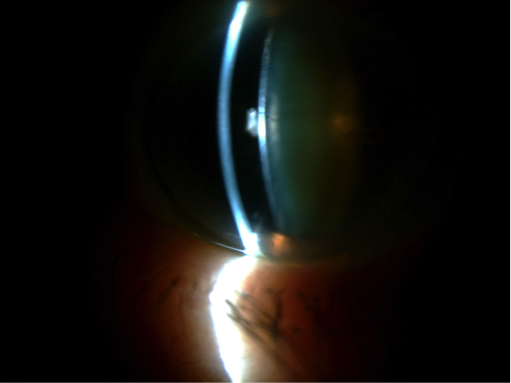

La queratoconjuntivitis epidémica es la forma más agresiva, suele ser bilateral y comienza entre 7 y 10 días tras el contacto (y el paciente puede ser contagioso durante los 10 a 14 días siguientes al inicio de los síntomas). Suele presentar reacción folicular en la conjuntiva, con petequias y en ocasiones hemorragias. La queratitis punteada epitelial es frecuente, muy molesta y en ocasiones dolorosa, pudiendo aparecer erosiones epiteliales grandes. La adenopatía preaucircular puede ser prominente, y entre la primera y segunda semana pueden presentarse infiltrados subepiteliales, debido a la reacción inmune provocada por el virus, causando fotofobia y mala visión que pueden persistir durante semanas.

Queratitis punteada epitelial